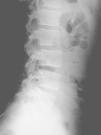

El nuevo estudio radiográfico demuestra espondilólisis L5 derecha y persistencia de integridad del hemiarco izquierdo (figs. 6 y 7). Igualmente, el estudio radiográfico dinámico demuestra establidad completa de la charnela lumbosacra (fig. 8). Por todo ello se planea el alta deportiva, aunque se le recomienda continuar un mes más el tratamiento, demorando el regreso a la práctica deportiva.

Figura 6

Figura 7